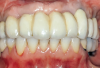

Fig 15. Maxillary arch with final prosthesis.

Figure 15

The implant-supported, screw-retained, hybrid acrylic complete denture in the maxilla and the mandibular implant fixed prostheses were delivered after torquing the custom abutments to 32 Ncm and the octa abutments to 35 Ncm, and metal frames, including the interlocks, were tried-in. After consensus was obtained on the phonetics, occlusion, and esthetics (Figure 15), the fit was verified by periapical radiographs. The patient, who was very satisfied with the result, was instructed in proper oral hygiene.